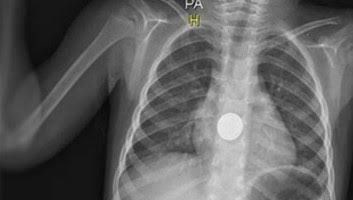

Bebek Düğme Yutarsa Ne Olur

Bebek Düğme Yutarsa Ne Olur.